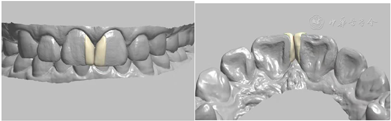

治疗计划为11、21贴面修复(邻面贴面)或正畸治疗。患者选择行贴面修复;龈上洁治,排龈,备牙前进行常规术前照相及比色(VITA2M2)。牙体预备:由11、21近中面扩展至唇近中线角,预备量约0.3 mm,基牙颈部预备与牙龈外形保持一致,肩台呈浅凹形,比色(VITA2M2)口扫;贴面试戴,邻接可,外形佳,与牙面边缘密合,色泽与天然牙匹配,患者满意同意粘接,粘结后检查正中颌、前伸颌及侧方颌,咬合无明显异常。见图3,图4,图5,图6,图7。

微创美学修复包括美学树脂,全瓷贴面以及本病例采用的邻面贴面修复方式。美学树脂修复式,采用不备牙或微备牙的方式,利用树脂材料修复缺损牙体。美学树脂修复优点:(1)对基牙磨除量少甚至无备牙;(2)能够恢复患牙的形态、颜色及邻接等。然而由于树脂具有易氧化的特性,其维持时间较瓷贴面短,同时,对于邻接及形态的恢复均依赖于医生的技术,因此大部分患者更愿意选择行瓷贴面修复。瓷贴面修复是指通过使用粘接剂将薄层瓷修复体固定于患牙唇面,以恢复牙体形态、改善色泽、关闭缝隙的微创美学技术[7]。传统瓷贴面需要从唇面预备牙体约为0.3~0.5 mm,邻面适当向舌侧预备,预备量较美学树脂修复大且术后可能会出现牙体敏感等症状。因此,随着数字化印模及CAD/CAM的发展,针对仅存在前牙散在间隙(<4 mm)的患者,借用美学树脂修复方式,采用邻面瓷贴面关闭缝隙既能获得美学修复的长期稳定性,又降低了因备牙量较多导致的牙敏感症状等术后并发症的发生率。

邻面贴面仅对牙齿的邻面部分进行牙体预备,最大限度的减少了对牙体组织的磨除量,满足了患者少磨牙的心理需求。同时,在其牙体预备过程中,越过唇舌面的线角的边缘线可以在重新塑形牙体外形的同时可以增加固位以及改善邻接。由于邻面贴面仅覆盖小部分牙面,所以修复体的颜色、质地和透光性都要应与天然牙相适应,以达到贴面与牙面在粘结区域自然过渡,以假乱真的程度,这也满足了患者对美学效果的需求。故对修复体的精度要求较高,要求术前拍摄记录和比色、粘接材料颜色的选择精确,同时制作过程中及时与技师的沟通交流,以达到较好的美学修复效果。